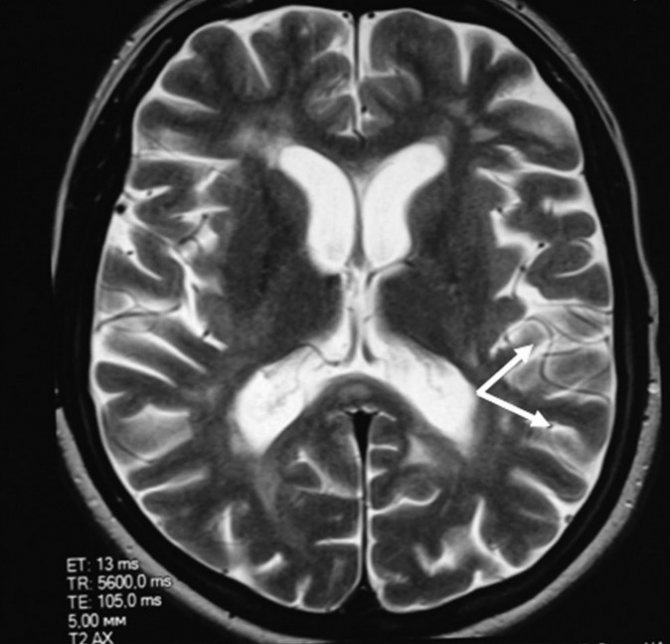

Магнитно-резонансная томография головного мозга позволяет сосчитать очаги глиоза. Томограммы показывают структуру участков. Чем обширнее фокус, тем больше клинических симптомов повреждения ЦНС.

Динамическое обследование (повторное МРТ) позволяет оценить увеличение размеров очагов головного мозга.

С помощью МРТ и КТ удается рассчитать количество нейроглиальных разрастаний на единицу объема церебральной ткани. Величина используется для оценки прогрессирования заболевания, оценки эффективности лечения.

Диагностика глиоза головного мозга

В большинстве случаев заболевание верифицируется случайно при сканировании головного мозга МРТ или КТ. Опасности формы не представляют. Повторное обследование через несколько месяцев проводится с целью изучения старых глиальных участков. Отсутствие увеличения размеров указывает на благоприятный прогноз.